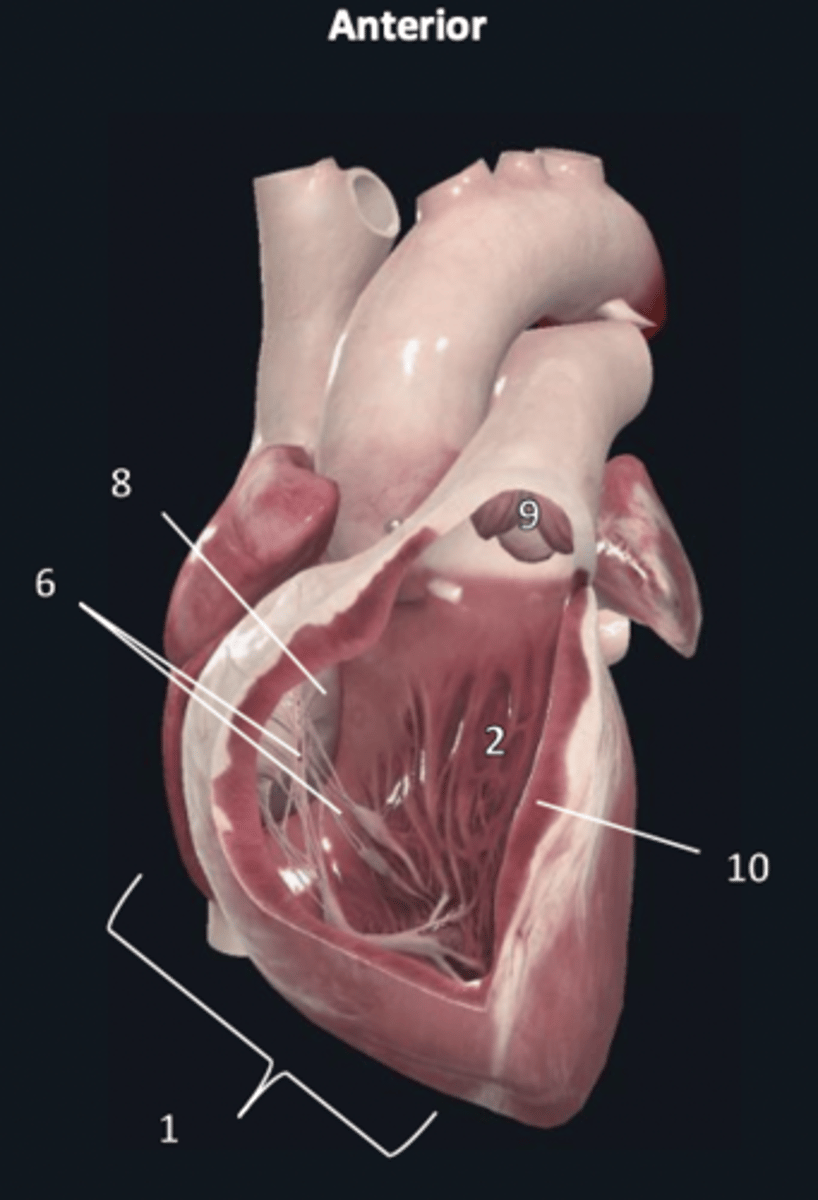

right ventricle

1

trabeculae carneae

2

septal papillary muscle

3

anterior papillary muscle

4

inferior papillary muscle

5

chordae tendineae

6

moderator band

7

tricuspid valve

8

pulmonary semilunar valve

9

interventricular septum

10